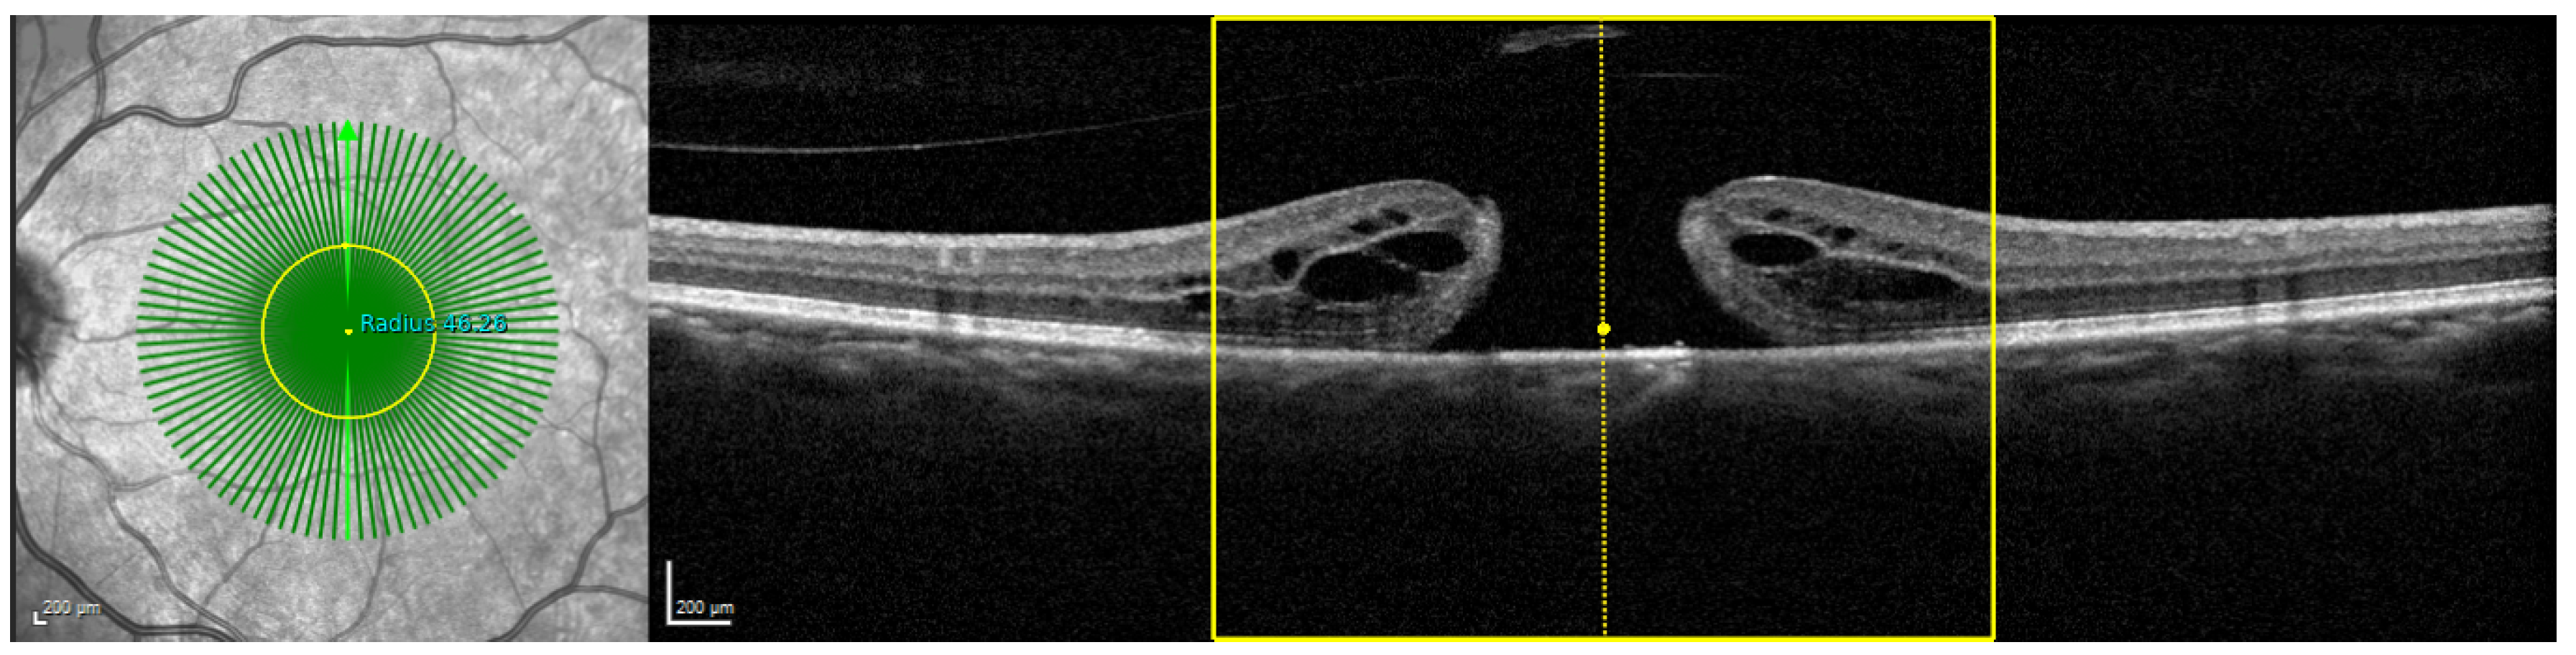

4.2. Detectability of the Asymmetry of Macular Holes due to 3D reconstruction

4.3. Comparison of Radial and Fused OCT Reconstruction